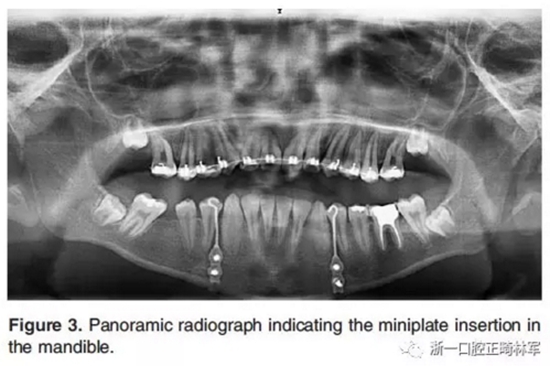

然后在全身麻醉下對所有患者進(jìn)行手術(shù)。在手術(shù)的第一步,在下頜兩側(cè)尖牙和第一前磨牙之間放置鈦板,并固定一個牽引鉤,位于尖牙和第一前磨牙的鄰間隙(Figure 2a,F(xiàn)igure 3)。手術(shù)的第二步,進(jìn)行不完全的Le Fort I截骨術(shù)以釋放上頜骨(Figure 2b)。Le Fort I截骨術(shù)中包括上頜骨的鼻腔外側(cè)壁,但鼻壁和鼻中隔保持完整,不包括翼板。